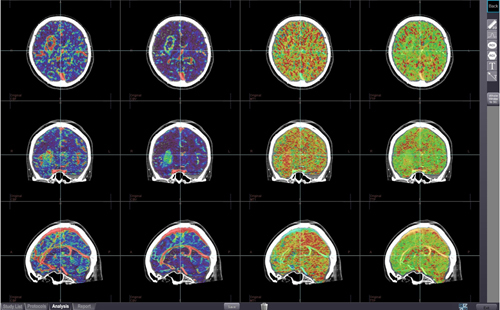

脳全体や広範囲のダイナミックCTから得られたボリュームデータを画像処理し,脳の血流状態を評価します。脳血流量(CBF)/脳血液量(CBV)/平均通過時間(MTT)/TDCから算出した造影剤到達ピーク時間(TTP)/平均通過時間(MTT:1st Moment法)を計測し,マッピングします。元画像と解析結果を重ね合わせて表示することや,サブトラクション結果画像を用いることで4Dの血管画像と解析結果を重ね合わせて表示することが可能です。

図4 CT脳血流解析(4D)